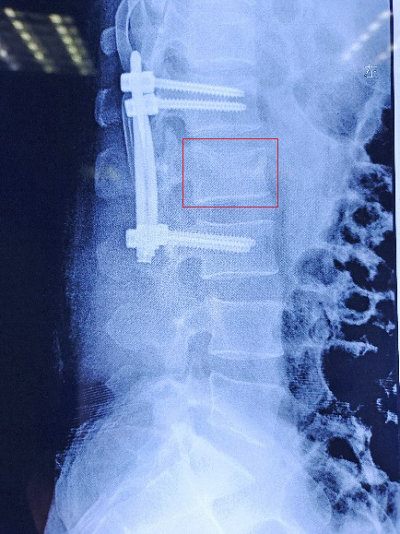

对患者进一步完善检查,无手术禁忌症,并展开术前讨论后进行手术。术前C臂透视下对椎体进行精确定位,并做好手术切口标记(C)。手术整个过程约1小时,手术过程顺利。患者术后双下肢感觉及活动正常,腰部仅4个1.5cm左右小切口(D)。术后第2天复查腰椎X线片,显示椎弓根钉位置良好,椎体压缩骨折已复位(E)。术后1周患者佩戴腰围下床活动。

E术后复查X线片